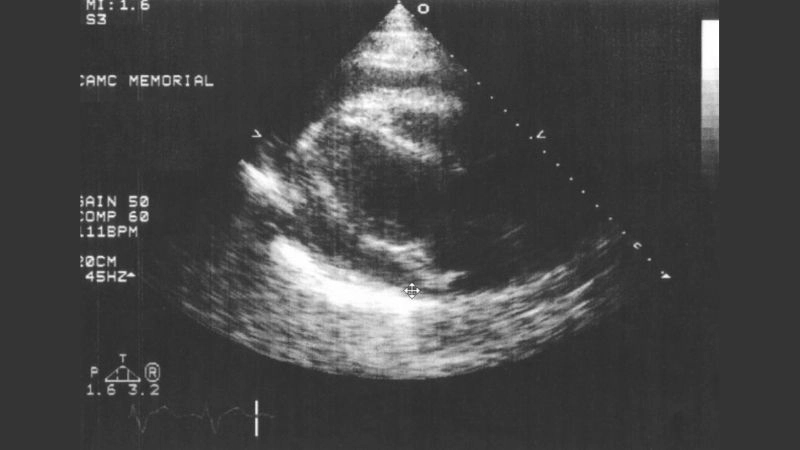

Images visual examples of Cardiac Contusion (Heart Trauma)

Visual examples often highlight areas of myocardial bruising on imaging scans or diagrams of heart injury.